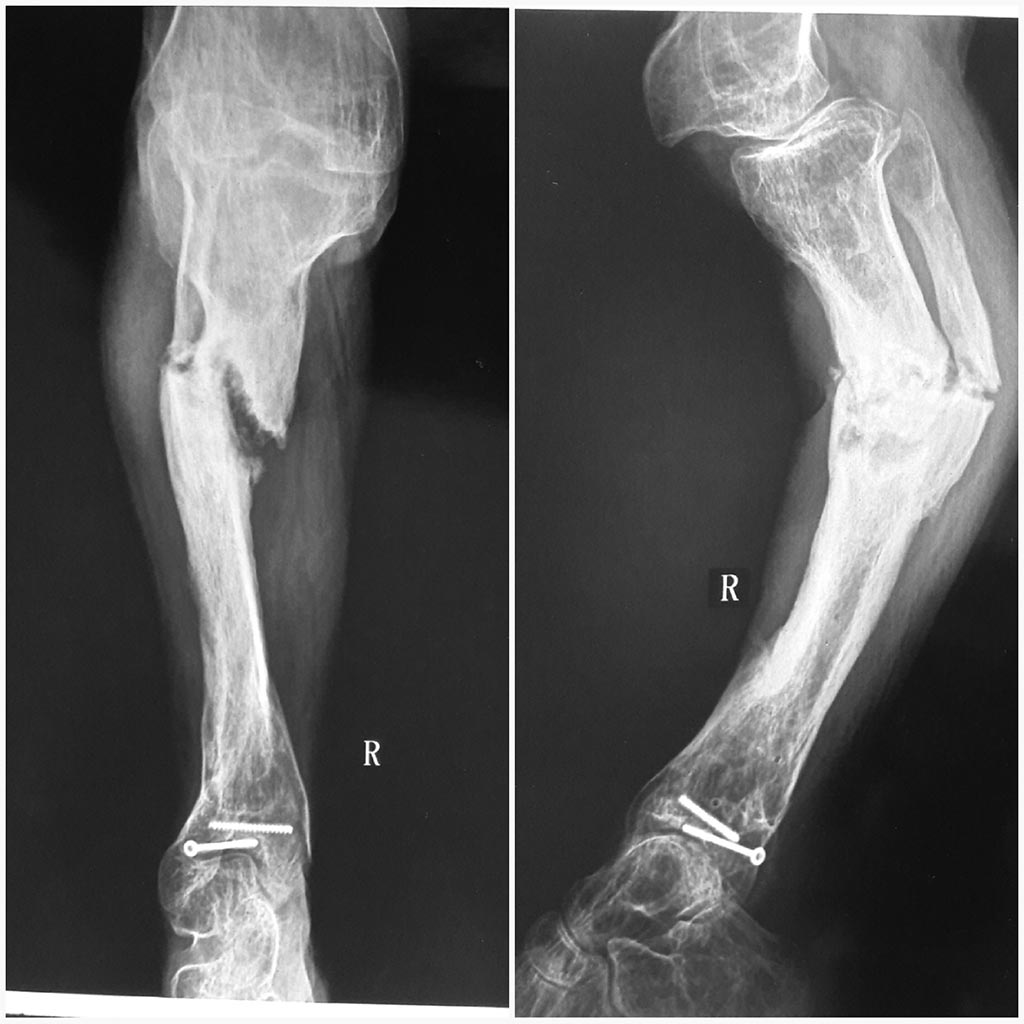

Больная 27 лет. В детстве перенесла острый гематогенный остеомиелит правой голени. Впоследствии образовался пателло-феморальный синостоз и отставание в развитии костей голени, варусная деформация голеностопного сустава за счет развития м/б кости. Укорочение голени было на 14 см.

В конце 2014 года в нашем отделении поэтапно произведено: корригирующая надлодыжечная остеотомия, фиксация накостной пластиной. Далее через 7 мес. удаление фиксатора, кортикотомия верхней трети большеберцовой кости с наложением аппарата Илизарова, постепенная дистракция аппаратом до 7см.

Недавно больная объявилась с жалобами на боли в области голени. При осмотре выраженное укорочение правой голени, деформация по типу рекурвации в в/3 голени, эквинусная деформация стопы (компенсаторная). Движения в коленном суставе - разгибание полное, сгибание 20º. На р-грамме ложный сустав в/3 большеберцовой кости с рекурвацией, пателло-феморальный синостоз.

В плане лечения мнения разделились. Планируем произвести резекцию ложного сустава, вскрытие костно-мозгового канала с наложением аппарата Илизарова, постепенное исправление деформации, выведение стопы в правильное положение. Далее желаем произвести БИОС большеберцовой кости.

Смущает синостоз надколенника и разгибательная установка коленного сустава. Как быть в таких случаях? Можно ли сбить надколенник с бедренной кости, поперечно распилить, произвести БИОС из этого доступа, а затем синтезировать надколенник по Веберу. Какие будут мысли на этот счет? Буду признателен любому мнению. Надеюсь на помощь сообщества.